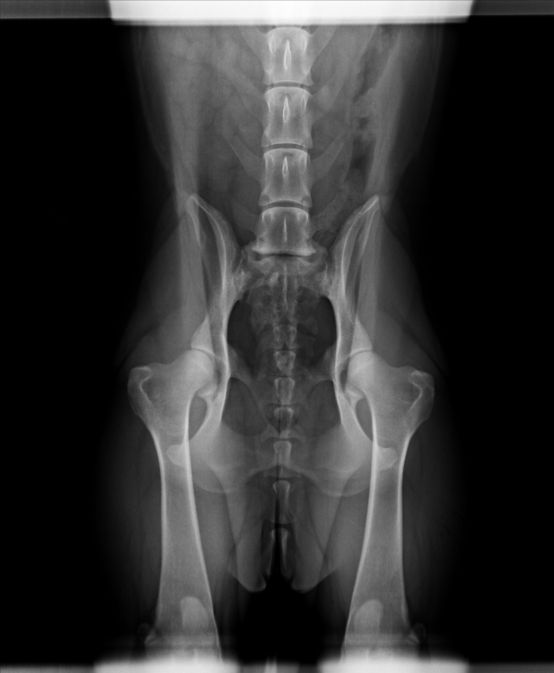

Radio de dysplasie de Plume

ADN : OUI Radio dyplasie : B |